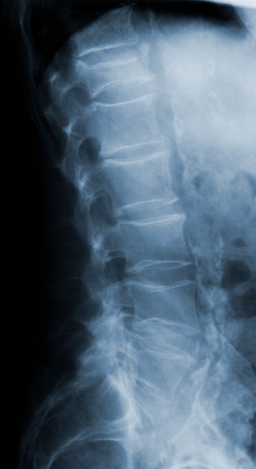

Для диагностики остеопороза используются рентгенография и денситометрия.

Рентгенологический метод исследования проводится на развернутой стадии развития заболевания.Развитие остеопороза оценивают зрительно по плотности изображения кости на рентгенограмме. Очаговый остеопороз представляет собой множество нечетко отграниченных участков разрежения костного вещества округло-овальной или многоугольной формы. При равномерном остеопорозе кость выглядит более прозрачной, костные перекладины истончены, общая картина губчатого вещества просматривается с трудом, а при резко выраженном процессе исчезает совсем.